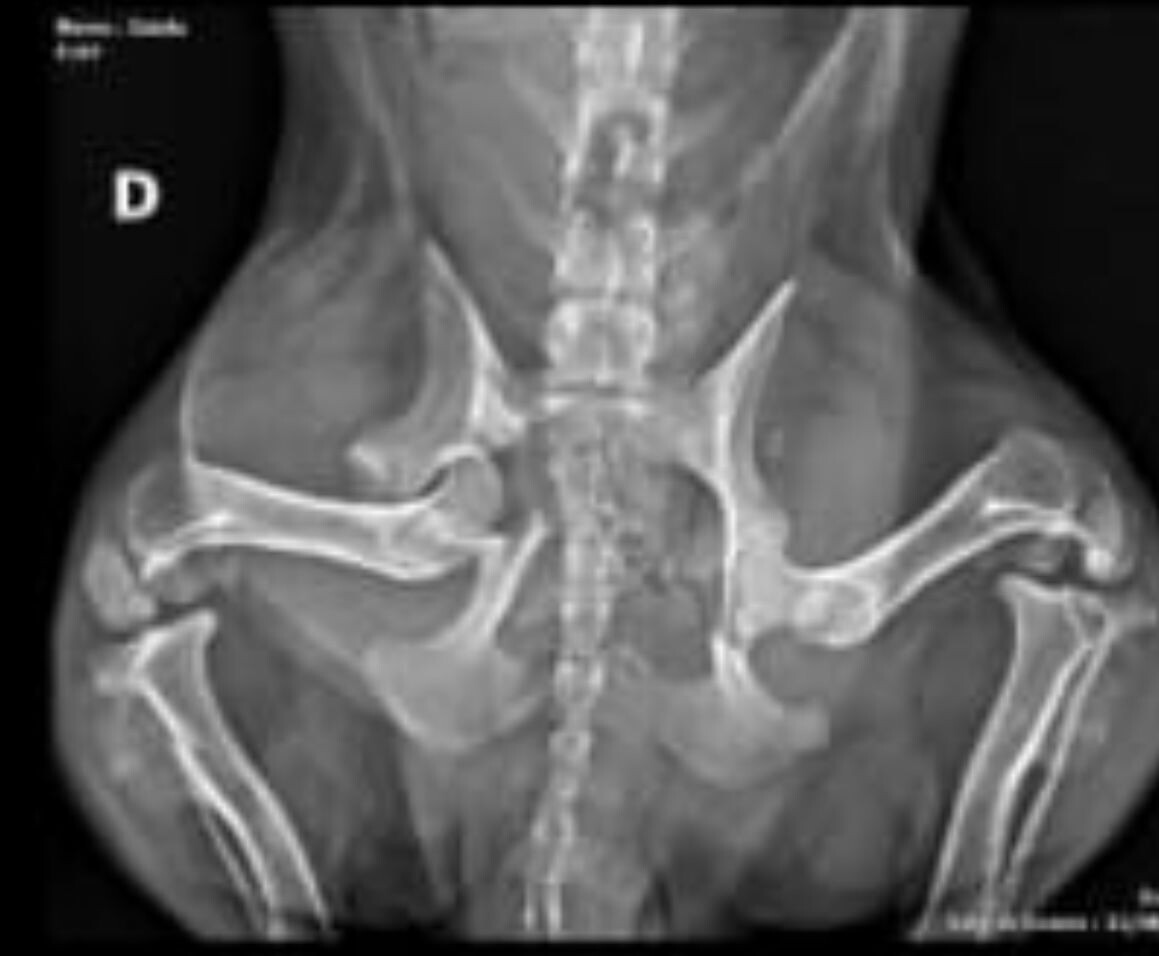

A novidade, pioneira na Região dos Lagos, representa um avanço no serviço oferecido pelo Canil, que já atua com atendimentos clínicos veterinários gratuitos e incentivo à adoção responsável. O serviço disponibiliza cirurgias mensais, seguindo critérios de gravidade e mediante necessidade. Os procedimentos são realizados em uma clínica parceira, que conta com uma estrutura equipada com centro cirúrgico e aparelho de raio-X, indispensável durante a correção de fraturas.